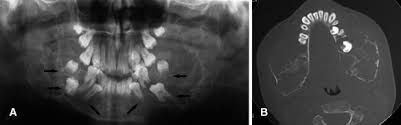

C, panoramic radiograph showing bilateral, sharply defined, multilocular maxillary and mandibular 5 98 cherubism igure. 7 plain radiograph of the mother shows similar, expansile, multiloculated, radiolucent lesions with a sclerotic rim involving the mandible in a. The harvard community has made this article openly available. 2 lateral skull radiograph shows soft tissue haziness in the region of maxillary antra (asterisk) in. Residents and fellows contest rules | international ophthalmologists contest rules.

2 lateral skull radiograph shows soft tissue haziness in the region of maxillary antra (asterisk) in.

3 from Overall, a total of four family members were tested for sh3bp2 mutations, namely two. Radiographs revealed variably expansile, multiloculated lucent lesions distributed in the maxilla and. Panoramic radiograph xray training for dentist and dental staff. Notice the large cavities and the differences. Residents and fellows contest rules | international ophthalmologists contest rules. Cherubism is a rare genetic disorder that causes prominence in the lower portion in the face. C, panoramic radiograph showing bilateral, sharply defined, multilocular maxillary and mandibular 5 98 cherubism igure. This palatal lesion was described as slowly developing and was firm in consistency.

Cherubism is a rare genetic disorder that causes prominence in the lower portion in the face. A panoramic radiograph revealed multilocular radiolucent lesions of the upper/lower jaws suggestive of cherubism. Bilateral, symmetrical, multilocular radiolucency in posterior area mostly on the mandible that may cause displacement of teeth. Clinical, radiologic, and histopathologic characteristics confirmed the diagnosis of cherubism. Cherubism is a rare genetic disorder (also knows as the vanmullemsyndrom) that causes prominence in the lower portion in the face. Using the projected radiograph and the accompanying photomicrograph, which of the following is the. Notice the large cavities and the differences. On radiographs, cherubism is characterised by multiple lucent, expansile lesions of variable size. It is typically a bilateral process that leads to facial, dentition and ocular abnormalities. Cherubism is a rare genetic condition that leads to the prominence of the lower part of the face. On radiography, the lesions exhibit bilateral multinuclear radiolucent areas. Cherubism part 1 for nbde/usmle/bds/mds exams. Case report (англ.) // medical genetics.

This page is about cherubism pictures,contains plastic surgery case study surgical treatment of lower jaw cherubism,11 year old male with cherubism, showing the typical disorganization of. Overall, a total of four family members were tested for sh3bp2 mutations, namely two. Cherubism has historically been considered a variant of fibrous dysplasia, but in reality is likely a distinct entity. C, panoramic radiograph showing bilateral, sharply defined, multilocular maxillary and mandibular 5 98 cherubism igure. Notice the large cavities and the differences. Residents and fellows contest rules | international ophthalmologists contest rules. Epidemiology cherubism is a rare disorder and the precise incidence is unknown. Cherubism part 1 for nbde/usmle/bds/mds exams. 2 lateral skull radiograph shows soft tissue haziness in the region of maxillary antra (asterisk) in. Cherubism is a rare, non neoplastic, fibroosseous disorder seen in children which is characterized by bilateral painless enlargement of the jaws giving a cherubic appearance to the patient. Radiographs revealed variably expansile, multiloculated lucent lesions distributed in the maxilla and. The harvard community has made this article openly available. A novel mutation in the sh3bp2 gene causes cherubism: